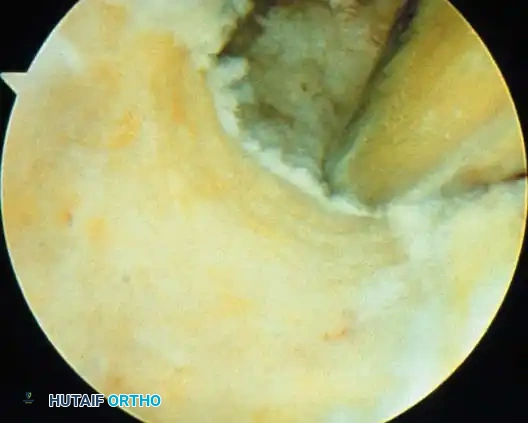

Intercondylar Notch The anatomical structures to be examined in the intercondylar notch are the anterior cruciate ligament, ligamentum mucosum, fat pad, posterior cruciate ligament, meniscofemoral ligaments, and intrameniscal ligament. With a cruciate ligament injury, it is crucial to observe the architecture and width of the notch with the knee fl exed 30 degrees (see Fig. 48-7G). An open, inverted U –shaped notch may increase the risk of disruption of the anterior cruciate ligament. As the arthroscope follows the horizon of the medial femoral condyle into the intercondylar notch and superiorly to the top of the intercondylar notch, the femoral origin of the ligamentum mucosum is seen. The ligamentum mucosum runs from the superior intercondylar notch down to the fat pad. It may be a thin, narrow band of synovium or a complete septum dividing the medial and lateral compartments. Diffi culty in passing the arthroscope from the lateral to the medial compartment and vice versa may be caused by an enlarged ligamentum mucosum or a complete septum. More commonly, the cause is a narrow synovial membrane superior and anterior to the anterior cruciate ligament. The cruciate ligaments within the intercondylar notch are best viewed with the knee fl exed 45 to 90 degrees. The femoral insertion of the posterior cruciate ligament should be inspected; it usually is covered by synovial tissue. Occasionally, the fi bers of the posterior cruciate ligament can be viewed and probed; hemorrhage or tearing of this synovial covering can be observed in posterior cruciate ligament avulsions. The anterior cruciate ligament is the most imposing structure in the intercondylar notch (see Fig. 48-7G). The tibial insertion and most of the ligament can be viewed adequately from this anterolateral portal. Viewing and exploration of the femoral attachment of the anterior cruciate ligament can be done best with the arthroscope through an anteromedial portal. The appearance of the anterior cruciate ligament varies from patient to patient, depending on its anatomy, the presence or absence of injury, and the synovial covering. Occasionally, the various anatomical bands of the anterior cruciate ligament appear as distinct bundles. In a normal anterior cruciate ligament, the synovial covering usually is thin, with small capillaries coursing on the surface that are obvious with close examination. If considerable synovitis is present, retraction of the ligamentum mucosum and other synovial tissues may be required to observe the underlying anterior cruciate ligament. With complete rupture of the anterior cruciate ligament, considerable hemorrhage within the synovial tissues is evident (Fig. 489A). If the synovial covering also has been ruptured, the collagen bundles of the anterior cruciate ligament are apparent as white “mop end” structures. In other instances, the synovial covering may be intact but hemorrhagic. Careful probing and opening of the synovial sheath often show disrupted anterior cruciate ligament bundles not evident during initial inspection. Probing the anterior cruciate ligament, opening its synovial sheath, and checking its tension with the probe are just as important as probing the menisci. A normal anterior cruciate ligament feels taut or “hard” when hooked with a probing instrument. A torn anterior cruciate ligament feels mushy, without tension.

Fig. 48-9 A, Complete tear of anterior cruciate ligament. B, Horizontal tear of degenerative lateral meniscus. C, Oblique tear of posterior horn of lateral meniscus. D, Incomplete radial tear of lateral meniscus. E, Degenerative tear of lateral meniscus. F, Resection of tear of lateral meniscus. Remaining tissue shows fatty degeneration.

The assistant can perform a drawer or a Lachman test while the anterior cruciate ligament is directly viewed. If torn, the ligament can be seen to provide no functional stability to anteroposterior translation of the tibia on the femur. Likewise, the posterior cruciate ligament should be examined and probed to confi rm integrity.